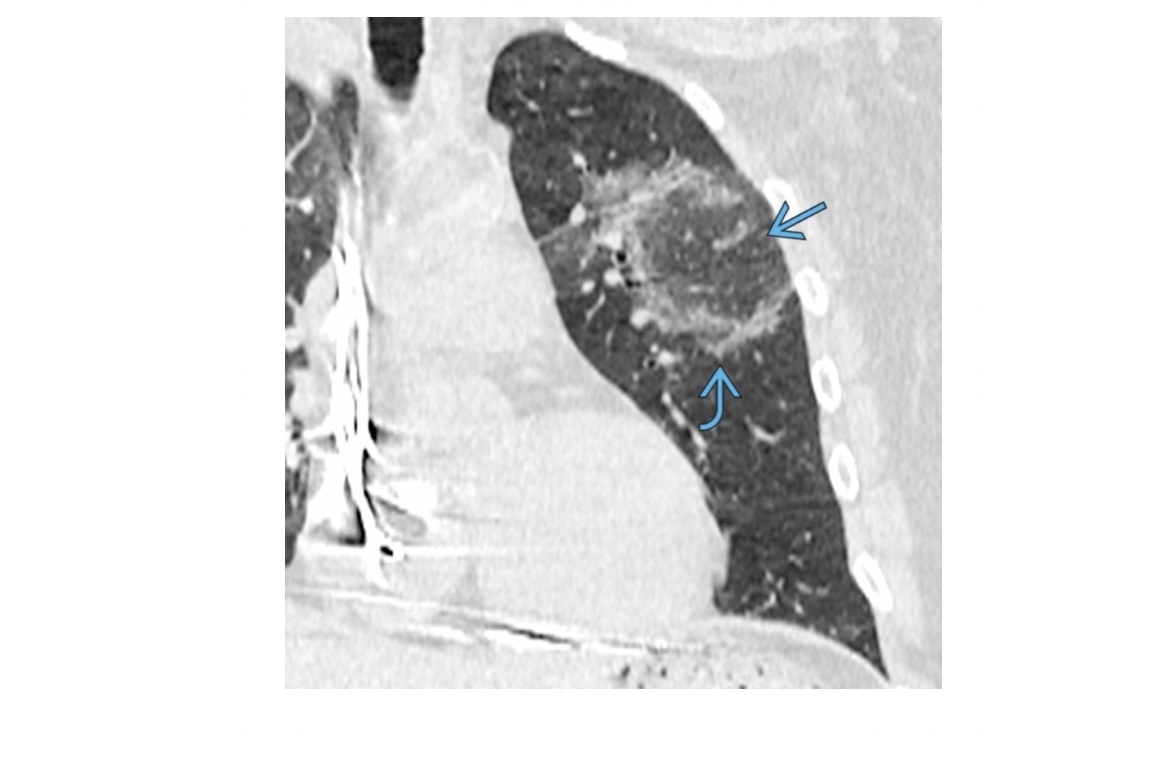

Round atelectasis

Comet tail sign

Adjacent to thickened pleural (assoacited with asbestosis) +/- Ca2+

can mimic a lung mass